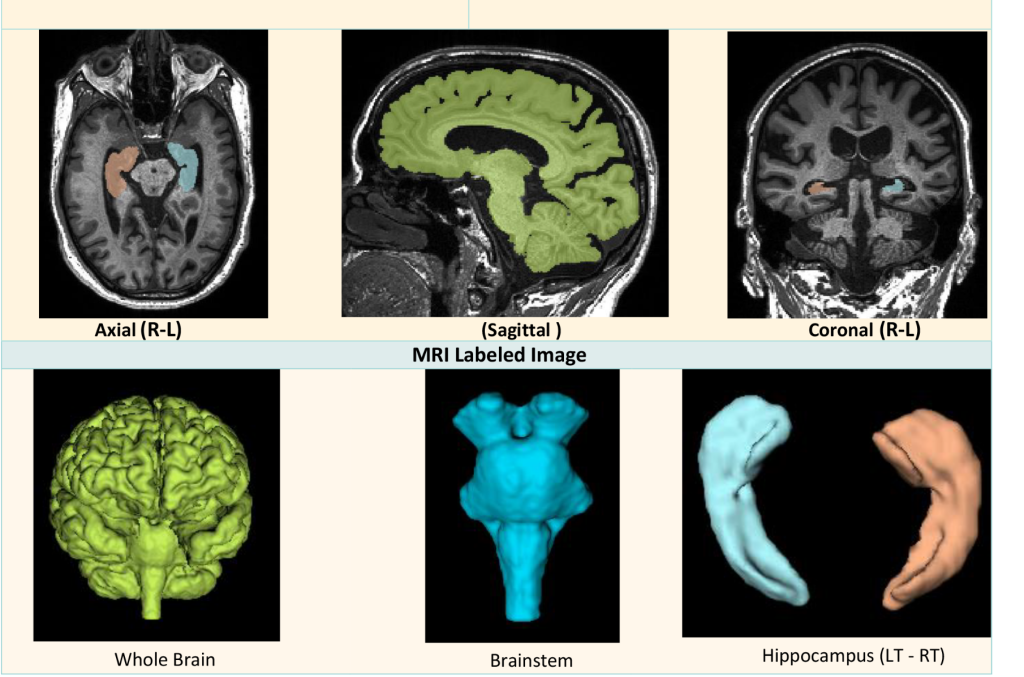

- In-Med Prognostics: Specializing in predictive analytics and diagnostic accuracy, particularly in neurological disorders, empowering clinicians with precise prognostic tools.

- BioCliq.ai: Delivering detailed reports with quantitative analysis and advanced 3D visualization for precise diagnosis and effective treatment planning. BioCliq solutions bridge the information gap regarding the patient’s condition between patients and clinicians, enhancing patient understanding and building confidence in the proposed treatment.